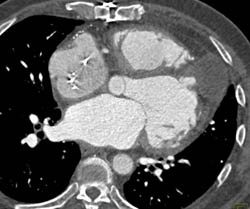

Normal Aortic Valve